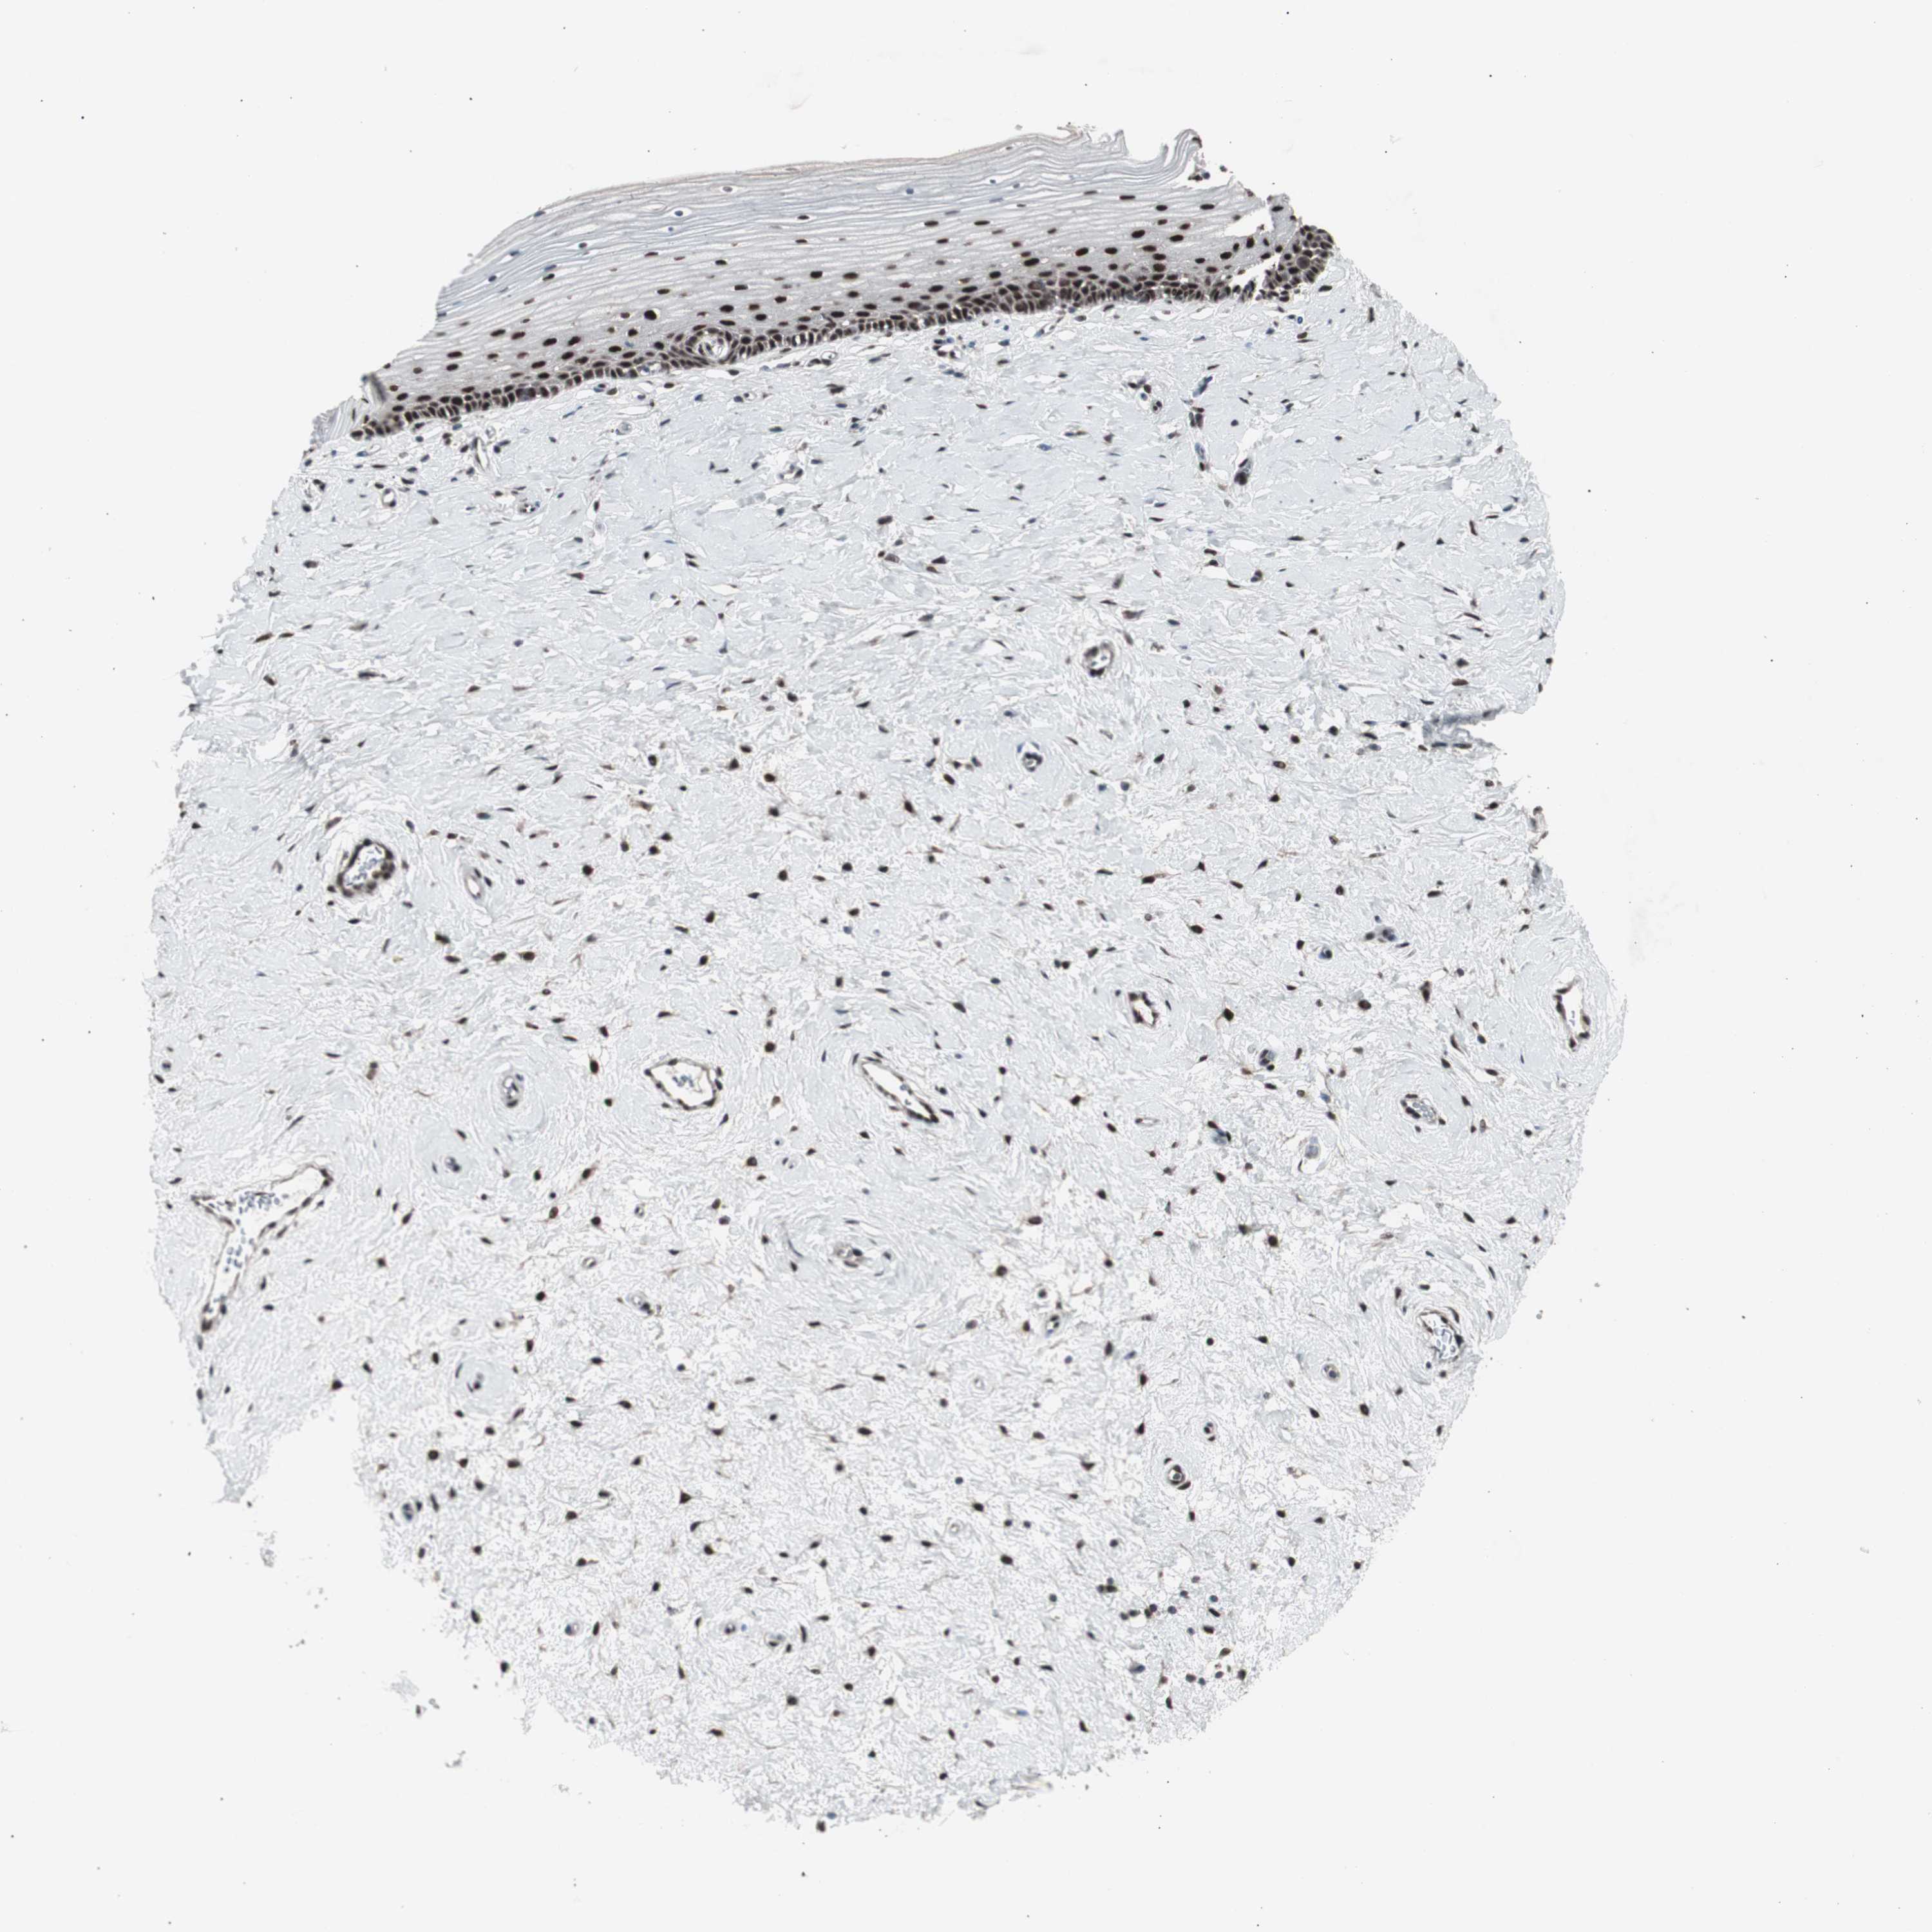

CERVIX - Antibody stainingi

Antibody staining in the annotated cell types in the current human tissue is reported as not detected, low, medium, or high, based on conventional immunohistochemistry profiling in selected tissues. This score is based on the combination of the staining intensity and fraction of stained cells.

Each image is clickable and will lead to virtual microscopy that enables deeper exploration of all samples and also displays staining intensity scores, fraction scores and subcellular localization as well as patient and tissue information for each sample.

Antibody CAB004565Antibody CAB005352

Glandular cells HighMedium

Squamous epithelial cells MediumHigh